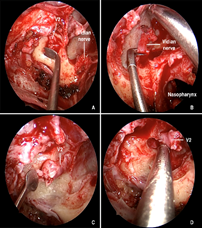

An 85-year-old male presented with a 6-month history of right hemifacial pain radiating to the ipsilateral ear, concomitantly with the onset of a skin lesion in the right malar region. He reported biopsy of a lesion in the same region 3 years ago, with local recurrence after 1 year, both resected with clear margins and a histopathological diagnosis of squamous cell carcinoma. MRI of the paranasal sinuses and brain showed a lesion consistent with tumor infiltration involving the infratemporal segment of the third branch of the right trigeminal nerve, extending to the foramen ovale and ipsilateral trigeminal cave, which was compressed (Figure 4) (Figure 5).

Figure 4 Magnetic resonance imaging, T1-weighted sequence with fat suppression. Coronal slices showing thickening and contrast enhancement in the right mandibular nerve (CN V3) at the level of the foramen ovale (blue arrow) and as it courses infratemporally within the masticator space (red arrow). The green arrow points to the normal contralateral foramen ovale for comparison purposes.

Figure 5 Magnetic resonance imaging, T1-weighted sequence with fat suppression. Axial slices showing anomalous contrast enhancement in the right foramen ovale (red arrow) when compared to the contralateral foramen (green arrow), consistent with involvement of the mandibular nerve (CN V3).

He underwent combined surgery for resection of the skin lesion, with clear margins on frozen section, and transnasal endoscopy for V3 nerve biopsy. At this stage, a post-lacrimal maxillectomy was performed with resection of the body of the right inferior turbinate down to the floor of the nasal cavity, thus providing better exposure of the posterior wall of the right maxillary sinus. A window was made into the posterior wall of the maxillary sinus, removing part of the underlying bone and periosteum to expose the structures of the pterygopalatine fossa. With the aid of the bipolar electrocautery and microdissection instruments, the relevant neurovascular structures (such as the pterygopalatine ganglion, foramen rotundum, internal maxillary artery and its branches) were isolated. This was followed by cauterization of the internal maxillary artery for hemostasis and better visualization of the operative field. The greater wing of the sphenoid was identified and dissected in the subperiosteal plane until the foramen ovale and CN V3 were visible (Figure 6). Finally, with the aid of grasping forceps, a biopsy of CN V3 was performed. Frozen sections identified carcinoma infiltrating nervous tissue. The final histopathological diagnosis was poorly differentiated squamous cell carcinoma.